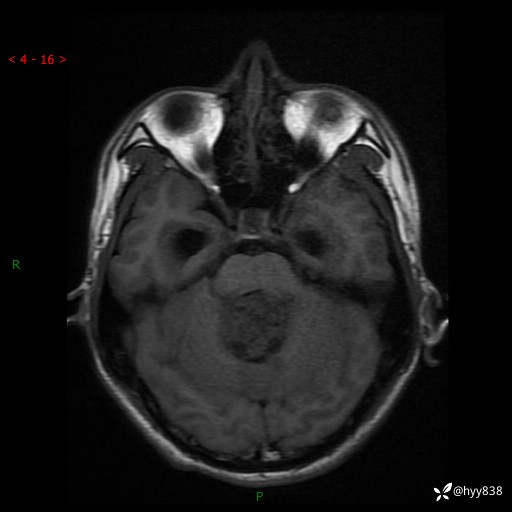

性别:男

年龄:17岁

简要病史:头痛伴间断性呕吐1月余,外院CT提示颅脑占位

颅脑MRI平扫+增强